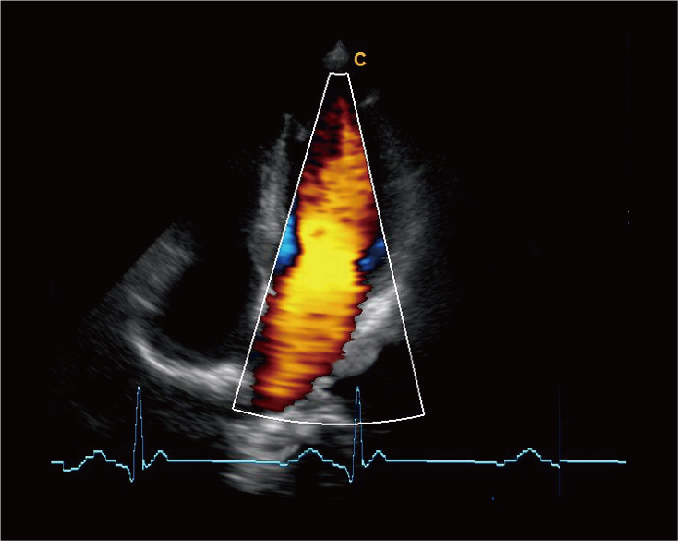

四腔心带 ECG